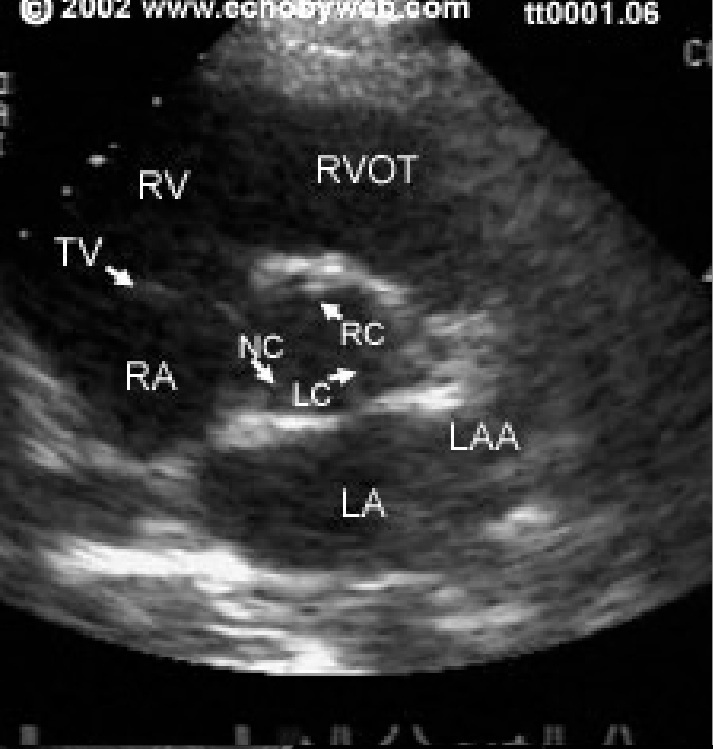

what are the atriventricular valves?

tricuspid and mitral

what are the semilunar valves?

pulmonic and aortic

which is the largest of the cardiac valves?

tricuspid valve